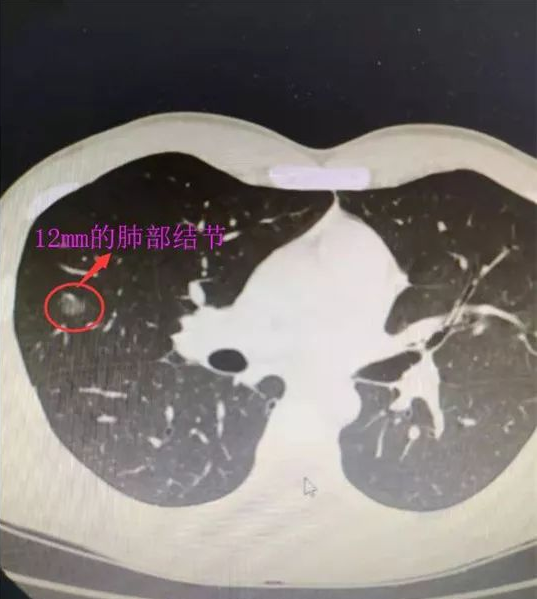

CT扫描结果让医生都紧张,小伙子两肺都有结节,其中右中肺上的结节有12mm。

根据形态观察,医生怀疑“肺癌可能”,这让他顿觉“怀疑人生”。

目前,很多体检查出来的肺结节患者都是早期或者早早期,这类患者在做了局部切除以后, 95%不会有复发和转移,临床上达到彻底治疗的目的。但是浸润性肺癌就有可能还有复发和转移。

因为胸片检查由于肋骨、锁骨的遮挡以及心脏的掩盖等,只能看到2cm以上的肿块,一些很小的、特殊部位的肿块看不到,只有通过胸部CT才能发现。对付肺癌,早期发现、早期诊断、早期治疗是最好的方法。